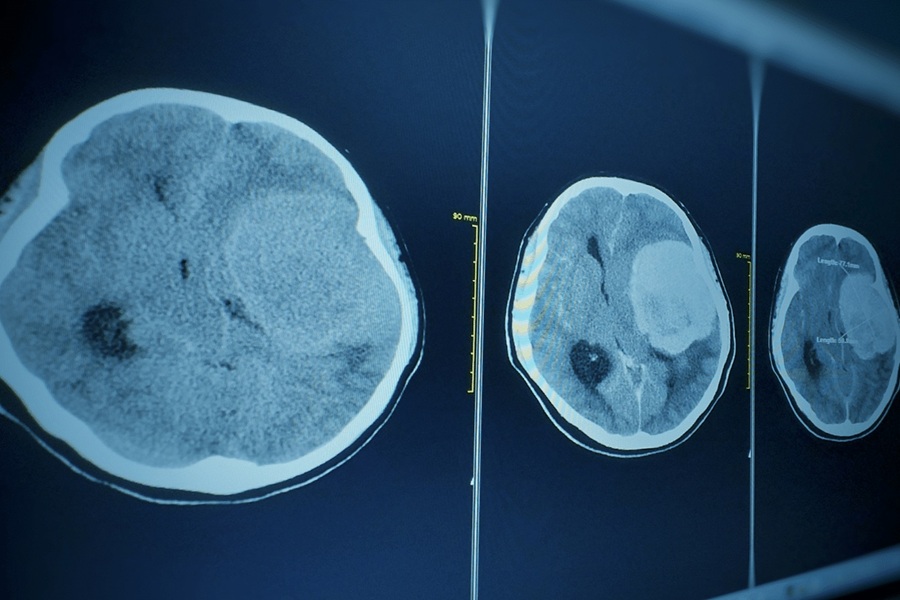

گلیوبلاستوما (Glioblastoma) که به عنوان آستروسیتوم درجه چهار نیز شناخته میشود، شایعترین و تهاجمیترین تومور اولیه مغزی در بزرگسالان است. ویژگی اصلی این تومور، رشد بسیار سریع و ماهیت نفوذی (Infiltrative) آن است؛ به این معنا که سلولهای تومورال به صورت میکروسکوپی به بافتهای سالم اطراف مغز تهاجم میکنند و ریشهکن کردن کامل آن را از طریق جراحی غیرممکن میسازند.

در تصاویر امآرآی، این تومور معمولا به صورت یک ضایعه حلقوی با مرکز نکروزه (Necrotic Core) دیده میشود. درمان استاندارد شامل جراحی برای برداشتن حداکثر حجم ممکن تومور (Debulking) و به دنبال آن پرتودرمانی همزمان با شیمیدرمانی با داروی تموزولوماید (Temozolomide) است. با وجود تمام این درمانها، پیشآگهی این بیماری همچنان ضعیف است.